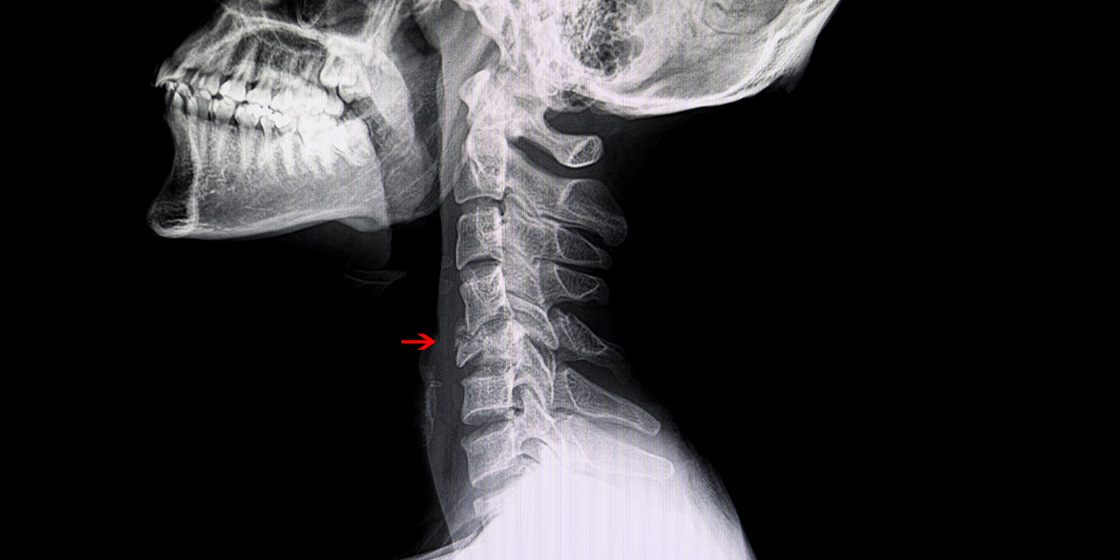

Compression Fracture Kyphoplasty Radiology . Treatment is usually observation and pain management. Spinal compression fractures occur as a result of injury, commonly fall onto the buttock or pressure from normal activities, to the weakened. Vertebroplasty and kyphoplasty are procedures used to treat painful vertebral compression fractures in the spinal column, which are a. Preprocedural magnetic resonance imaging (mri) is preferred to document bone marrow edema on short tau inversion recovery. Determining the acuity of a fracture requires an mri or bones scan. Osteoporotic vertebral compression fractures frequently result in significant morbidity and health care resource use. Vertebroplasty and kyphoplasty are methods interventional radiologists use to help pain from spine and other bony tumors, or pain caused by. Vertebroplasty (vp) and kyphoplasty (kp) are two percutaneous interventional. For patients with severe and.